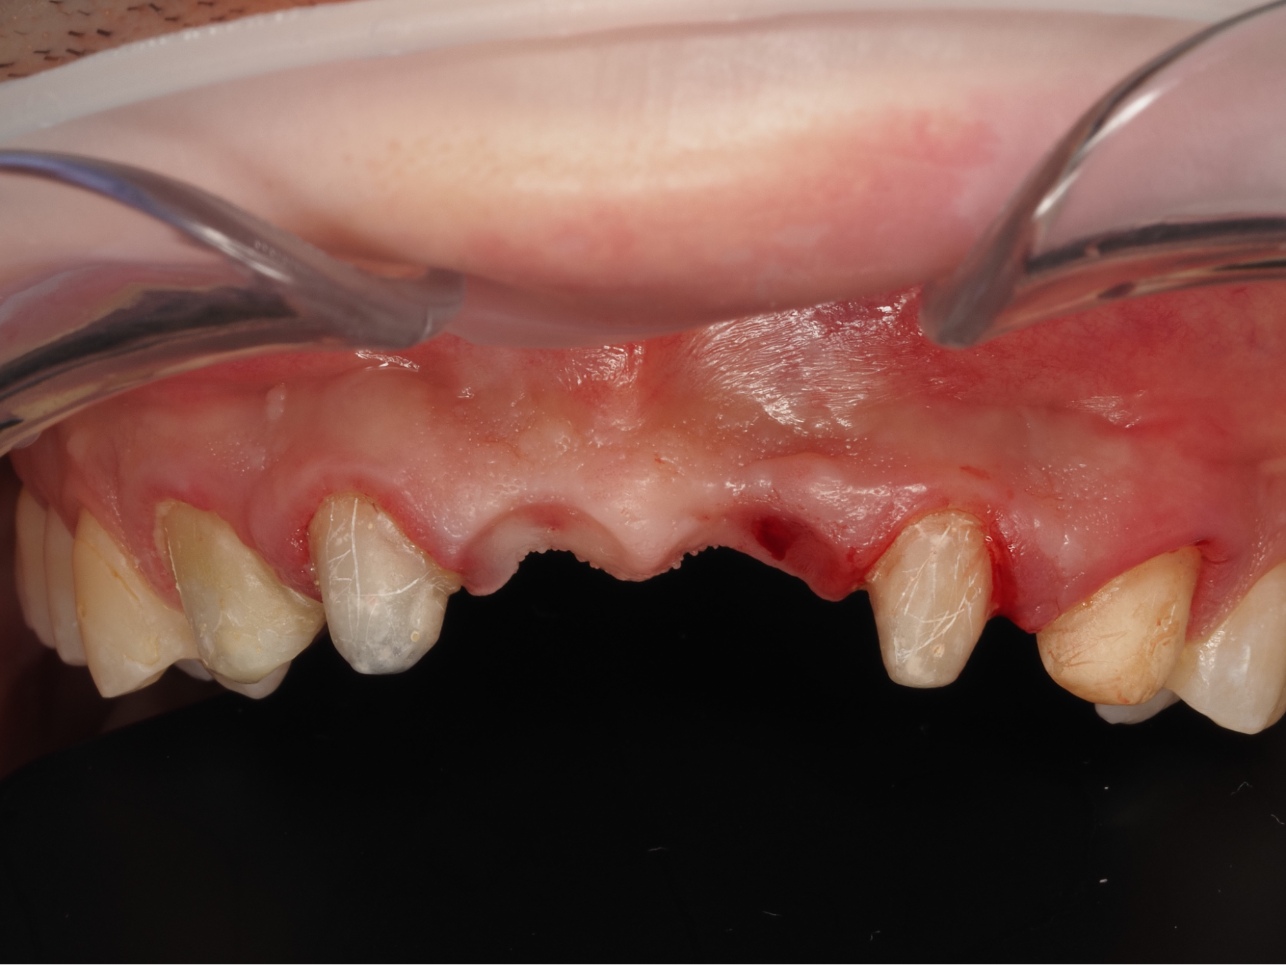

Zanik kości szczęki – Kość szczęki w miejscu brakującego zęba zanika, ponieważ nie jest naturalnie obciążana. Powoduje to, że twarz traci naturalne podparcie, policzki mogą opadać, a to prowadzi do zmiany rysów i starczego wyglądu.

Utrata zęba uruchamia lawinę problemów. Procesów tych często nie da się cofnąć, a jedynie zatrzymać poprzez uzupełnienie braków implantem. Długotrwałe zwlekanie z decyzją może znacząco utrudnić i podnieść całkowity koszt przyszłego leczenia implantologicznego.

Najczęściej pierwszymi utraconymi zębami są tzw. „szóstki” – czyli pierwsze zęby trzonowe. Ze względu na wczesne wyrzynanie i trudniejszą higienę, często ulegają one zniszczeniu, a ich utrata w dorosłym wieku jest statystycznie bardzo częsta.

„Szóstki” to jednak nasze największe i najsilniejsze zęby, stworzone po to, by przejmować główne siły zgryzowe. Ich brak zaburza równowagę całego zgryzu i ma poważne konsekwencje dla pozostałych zębów:

Choć utraconej „szóstki” może nie widać w uśmiechu, koszt jej braku w perspektywie czasu jest ogromny. Zdecydowanie przewyższa on cenę implantu zęba.